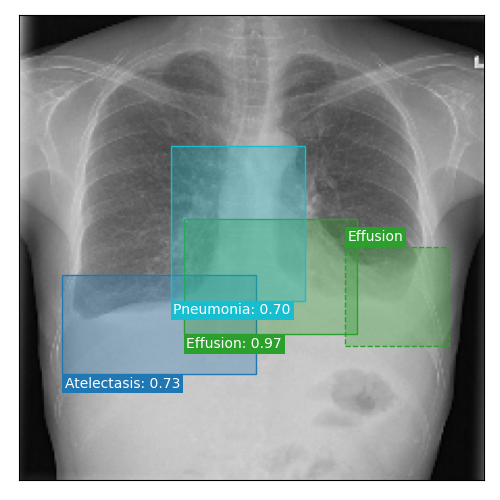

Qualitative Results

As shown in Fig. 4 Loc-ADPD detects cardiomegaly almost perfectly, as it is always exactly localized at one anatomical region. Other pathologies are detected but often with too large or too small boxes as they only cover parts of anatomical regions or stretch over several of them, which cannot be completely corrected using WBF. Detection also works well for predicting several overlapping pathologies. For qualitative comparisons between Loc-ADPD and MIL-ADPD, we refer to Appendix 0.B.